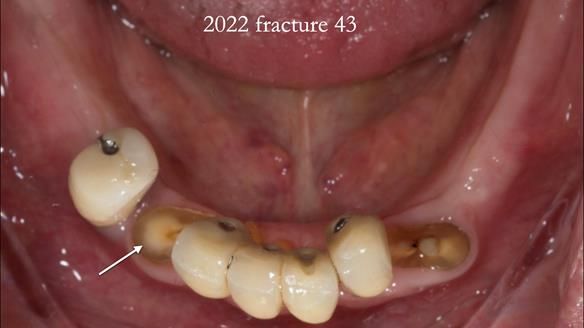

In 2022, tooth 43 fractured.

An artificial tooth was added to the RPD

by welding a cobalt–chrome tag to the bar

and adding the tooth.

The denture continued to function extremely well.